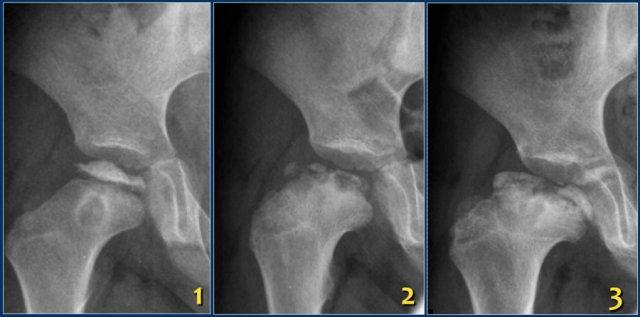

Các hình ảnh cho thấy bệnh Perthes khớp háng phải ở một bé trai năm tuổi.

Các dấu hiệu bao gồm:

- Đầu xương đùi dẹt và xơ cứng.

- Gãy xương dưới sụn, được đánh giá rõ nhất trên tư thế chụp nghiêng kiểu ếch.

Các hình ảnh cho thấy:

- Xẹp và xơ cứng chỏm xương đùi kèm vùng thấu quang ở hành xương.

- Tiến triển đến vỡ vụn và hình thành cổ xương ngắn, rộng.

- Biến dạng coxa magna đang hình thành.